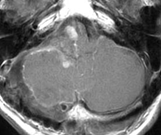

以下の画像に呈示するような脳幹や小脳を圧迫する大きい腫瘍に対しては、開頭手術が優先されます。手術中に神経刺激装置・聴性脳幹反応など電気生理学的モニタリングを併用し、1つ1つの手術操作によって神経機能を損傷していないか随時チェックしながら手術を行っており、術後後遺症の予防に努めています。